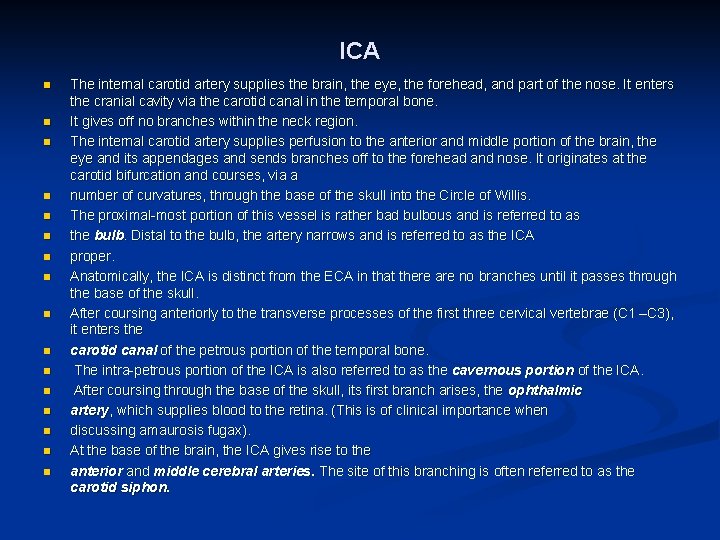

ICA n n n n The internal carotid artery supplies the brain, the eye, the forehead, and part of the nose. It enters the cranial cavity via the carotid canal in the temporal bone. It gives off no branches within the neck region. The internal carotid artery supplies perfusion to the anterior and middle portion of the brain, the eye and its appendages and sends branches off to the forehead and nose. It originates at the carotid bifurcation and courses, via a number of curvatures, through the base of the skull into the Circle of Willis. The proximal-most portion of this vessel is rather bad bulbous and is referred to as the bulb. Distal to the bulb, the artery narrows and is referred to as the ICA proper. Anatomically, the ICA is distinct from the ECA in that there are no branches until it passes through the base of the skull. After coursing anteriorly to the transverse processes of the first three cervical vertebrae (C 1 –C 3), it enters the carotid canal of the petrous portion of the temporal bone. The intra-petrous portion of the ICA is also referred to as the cavernous portion of the ICA. After coursing through the base of the skull, its first branch arises, the ophthalmic artery, which supplies blood to the retina. (This is of clinical importance when discussing amaurosis fugax). At the base of the brain, the ICA gives rise to the anterior and middle cerebral arteries. The site of this branching is often referred to as the carotid siphon.